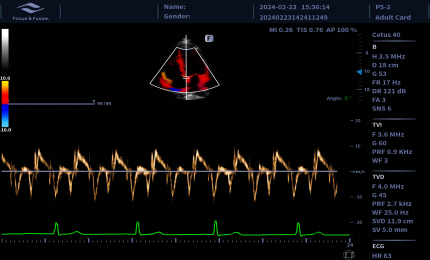

Obrazowanie tkankowe metodą Dopplera

Obrazowanie tkankowe metodą Dopplera (TDI) to solidne i powtarzalne narzędzie echokardiograficzne, które wykorzystuje efekt Dopplera do oceny charakterystyk ściany mięśniowej w całym cyklu sercowym, obejmując prędkość, przemieszczenie, deformację oraz timing zdarzeń. Pozwala na ilościową ocenę zarówno globalnej, jak i regionalnej funkcji oraz timing zdarzeń miokardialnych.